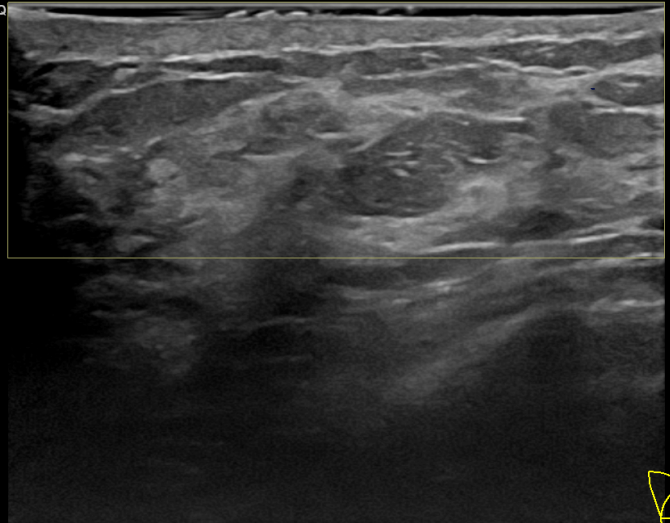

상기환자는 외부검진이상으로 내원하신 30대후반

여성분으로 의심스러운 우측혹 조직검사 시행해 상피내암 으로 진단되었습니다